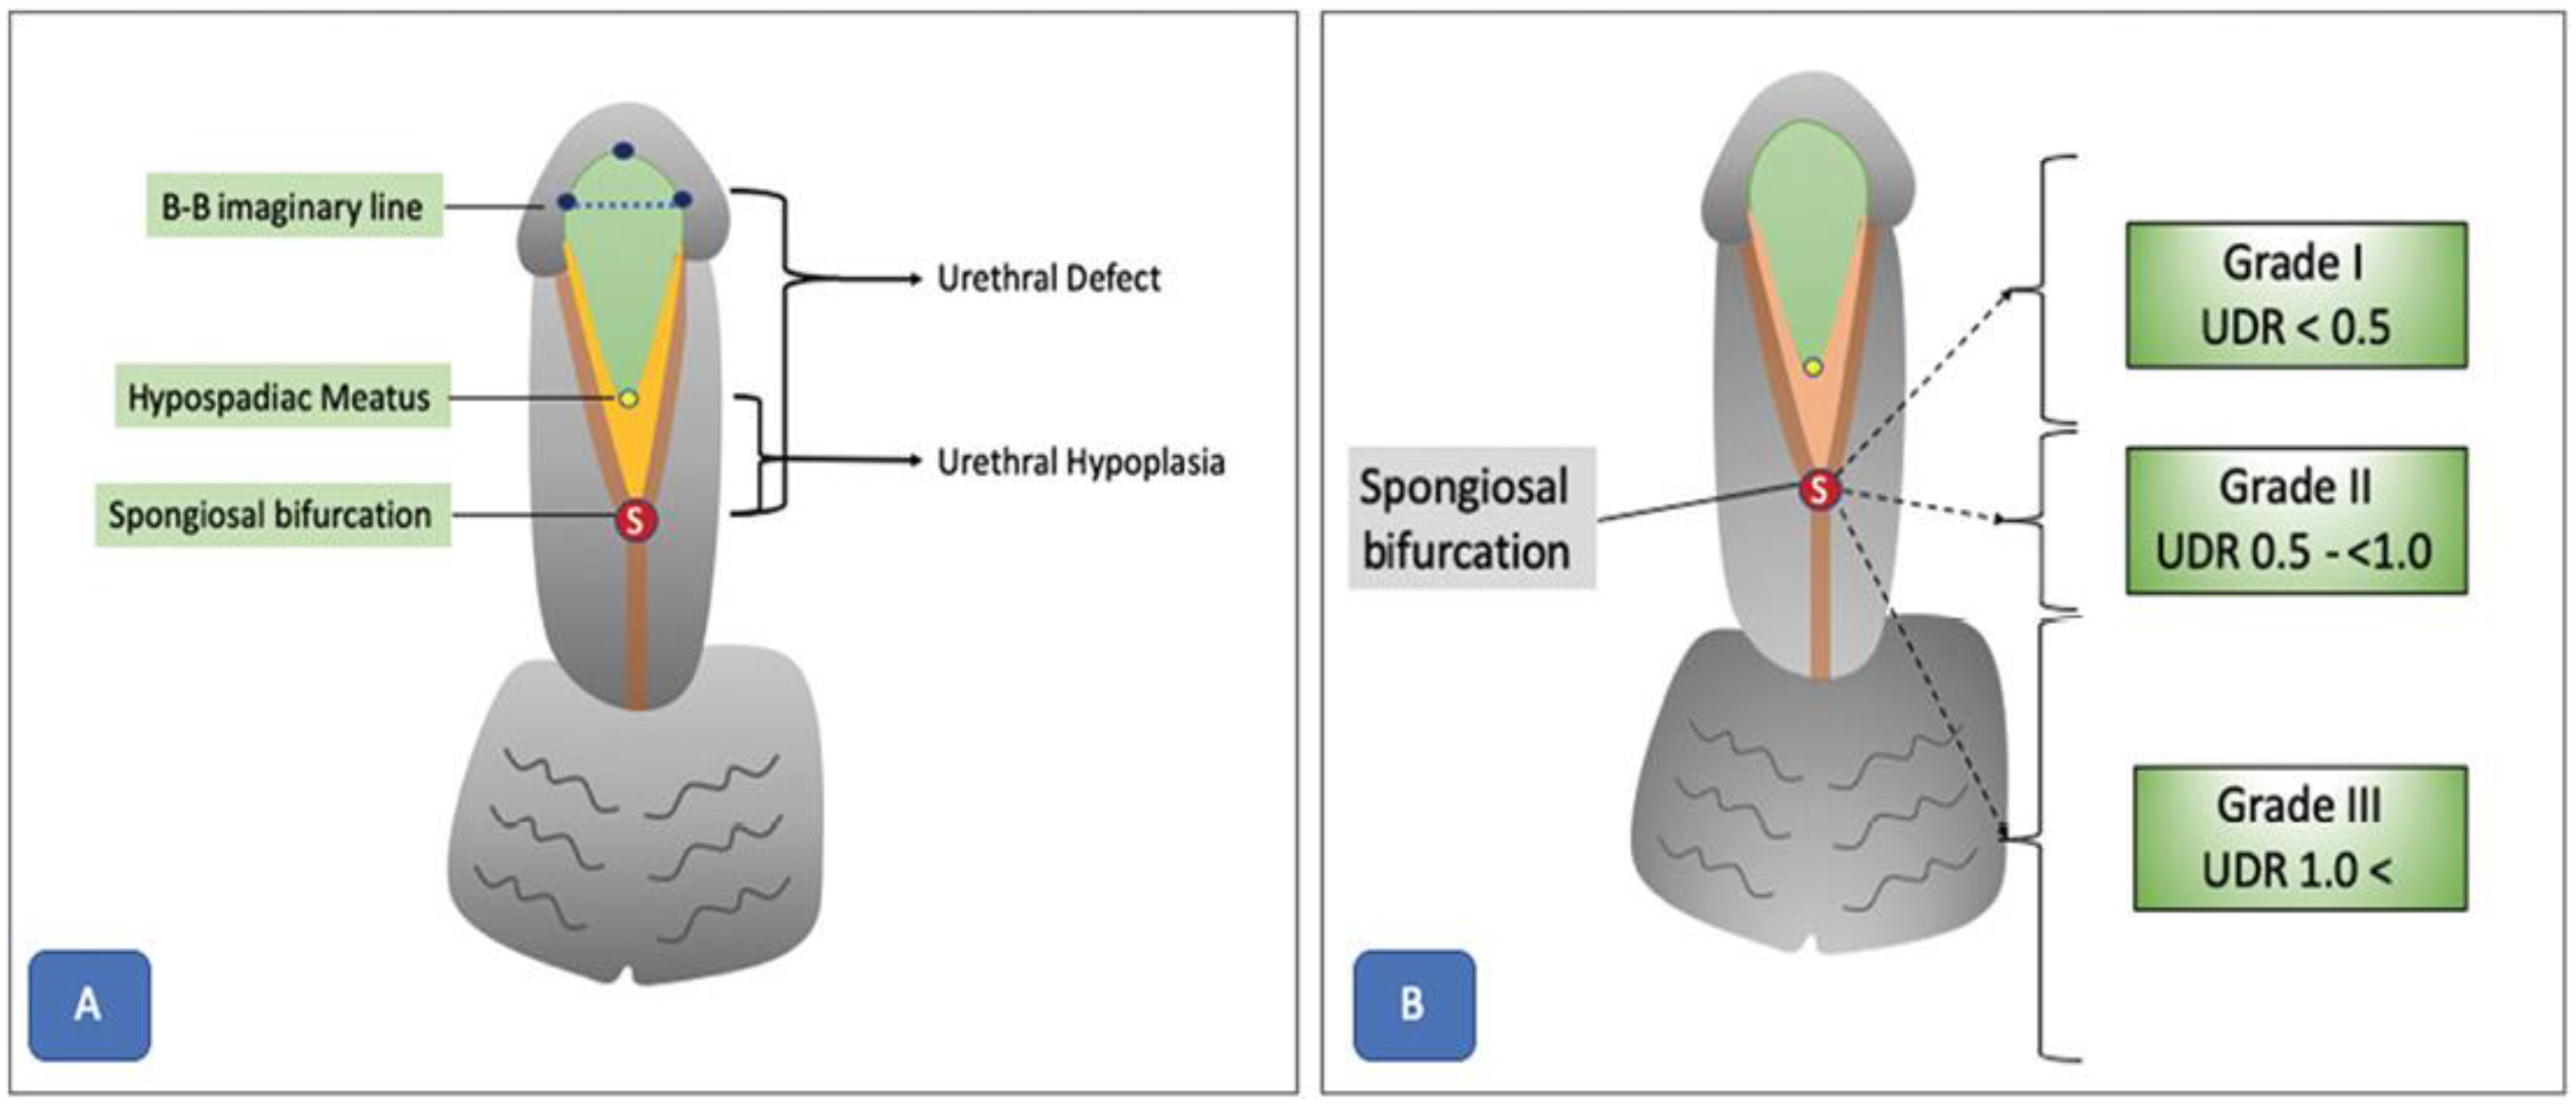

8. Hypospadias

8.1. Surgical Considerations and Complications

- Objective assessment of hypospadias severity: Objective evaluation methods such as the plate objective scoring tool (post) represent major advances in the field of hypospadias surgery [76]. POST provides a systematic way to assess urethral plate quality, which helps surgeons select appropriate repair methods and anticipate postoperative results. However, even standardized methods like POST remain subjective, notably regarding the interpretation of anatomical landmarks from 2D pictures [77]. The need for accurate and reproducible methods to standardize evaluation and reduce variability between surgeons is therefore clear. Objective evaluation methods like POST are an important step towards this aim, but additional refinement and validation are required before they can be used widely in clinical practice.

- Surgical considerations in hypospadias-associated penile curvature (HAPC): The treatment of hypospadias-associated penile curvature (HAPC) is complex, as explained by Fernandez et al. (2021) [78]. Critical aspects are the initial assessment and quantification of HAPC, where variable evaluation techniques highlight the need for standardized, reliable, and repeatable instruments. The lack of agreement on surgical correction thresholds also affects decision making. Surgical method selection can range from dorsal plication to ventral lengthening operations, as described by Abbas et al. (2023) [76]. The complications linked with HAPC correction, such as graft contracture and recurrent curvature, demand careful planning and judicious use of surgical procedures. Overall, treating HAPC requires a multimodal strategy that includes several standardized evaluation tools, evidence-based protocols, and careful surgical method selection.

- Impact of anatomical variables on surgical outcomes: Anatomical characteristics are critical determinants of surgical results and potential problems in hypospadias correction, as highlighted by Fruntelata and Stoica (2021) [79]. Fernandez et al. (2021) [78] reported that the glans size, quality of the urethral plate, and degree of penile curvature all exert a major impact on surgical difficulty and the likelihood of attaining good esthetic and functional outcomes. These studies present information on the many kinds of hypospadias operations performed and their related consequences, emphasizing the need to conduct preoperative screening for concomitant abnormalities and tailor surgical techniques accordingly. Despite acknowledgement that these anatomical features are key predictors of surgical results, there is still substantial subjectivity in their evaluation, making it difficult to standardize categorization criteria and compare outcomes between surgical facilities and individual procedures. Addressing these issues necessitates continued work to provide uniform screening tools, improve categorization criteria, and establish evidence.

8.2. AI Applications in Hypospadias Surgery

- AI-based UP quality assessment: Abbas et al. (2023) [76] explored the potential of AI and DL algorithms to streamline and optimize the assessment of urethral plate (UP) quality from 2D images. The authors proposed a framework that combines glans localization, landmark detection, and plate objective scoring tool (POST) calculation using DL models. The localization step detects the glans area within an image using a YOLOv5 network, which achieved highly accurate results (mean average precision 99.5%, overall sensitivity 99.1%). Isolating the region of interest from image background improves the feature extraction and landmark detection in subsequent stages.

- Landmark detection and benefits: For landmark detection, authors employed a deep convolutional neural network (CNN) architecture called HRNetV2, which maintains high-resolution representations throughout the network [76]. This approach results in spatially precise landmark predictions, which are essential for accurate calculation of the POST score. The proposed model achieved a normalized mean error of 0.07152 in predicting the coordinates of all five POST landmarks. The authors highlighted the potential benefits of this AI-based framework in increasing inter-rater consistency and standardizing UP quality scoring. Less experienced surgeons could benefit from the real-time intraoperative application of the algorithm to aid decision making and potentially improve postoperative outcomes.

- AI for hypospadias parameter recognition: Wahyudi et al. (2022) [80] proposed the development of an artificial neural network (ANN) for the automated recognition of various hypospadias parameters from digital images. The key parameters include hypospadias status, meatal location and shape, urethral plate quality, glans diameter, and glans shape. This type of model needs to be trained on a database of labeled images from hypospadias cases and normal penile anatomy controls. To achieve this, parents or guardians capture standardized photographs using a mobile app, then upload these for analysis by the ANN model. Performance can then be validated against evaluations by pediatric urologists, with measures including accuracy, precision, and inter-rater reliability. Several other AI-based approaches have been proposed to help standardize hypospadias assessment, reduce interobserver variability, and facilitate diagnosis, especially in regions with limited access to specialized healthcare personnel (Table 7).Table 7. Recent AI applications in hypospadias surgery.

Application Description Key Benefits AI-based UP quality assessment [76] Combines glans localization, landmark detection, and POST score calculation using DL models for assessing urethral plate quality from 2D images Increases inter-rater consistency, standardizes UP quality scoring, aids decision making for less experienced surgeons Landmark detection [76] Uses HRNetV2 deep CNN architecture for spatially precise landmark prediction, essential for accurate POST score calculation Enables accurate POST score calculation by precisely localizing anatomical landmarks AI for hypospadias parameter recognition [80] Proposes an AI system using an artificial neural network (ANN) for automated recognition of hypospadias parameters from digital images, including meatal location, urethral plate quality, and glans characteristics Standardizes hypospadias assessment, reduces interobserver variability, facilitates diagnosis in areas with limited access to specialists Deep learning for hypospadias surgery planning [81] Developed a DL model to predict the likelihood of requiring additional surgical procedures based on preoperative patient data and intraoperative findings Helps in preoperative planning and counseling by predicting the need for additional procedures AI-assisted hypospadias classification [82] Developed a convolutional neural network (CNN) model for automated classification of hypospadias severity from clinical photographs Enables objective and consistent classification of hypospadias severity, which can guide surgical decision making Automated glans size measurement [78] Proposed an AI-based method for automated measurement of glans size from digital photographs, a critical parameter in hypospadias surgery planning Provides accurate and reproducible glans size measurements, reducing interobserver variability and facilitating surgical planning